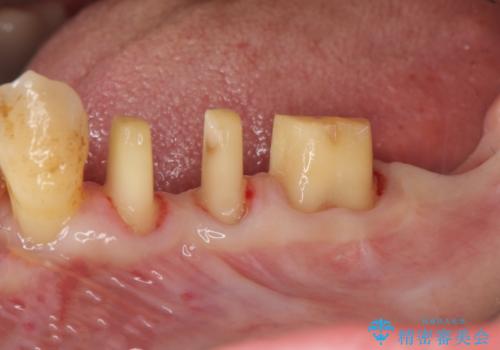

歯周病再生治療と歯周ポケット除去 歯周外科手術

- 他院で歯周病を指摘され、様子見ではなく根本的な治療はないか?とご相談に来院されました。

重度の歯周病で再生療法の適応ではない最後方臼歯は抜去行い、インプラント治療、

がたつきの強い天然歯を矯正治療で整えたのち、再生治療、歯周ポケットを除去する歯周外科手術を行いました。

歯周病の問題が解決したのち、歯の揺れを抑えるべくセラミッククラウンで連結補綴をおこなっています。